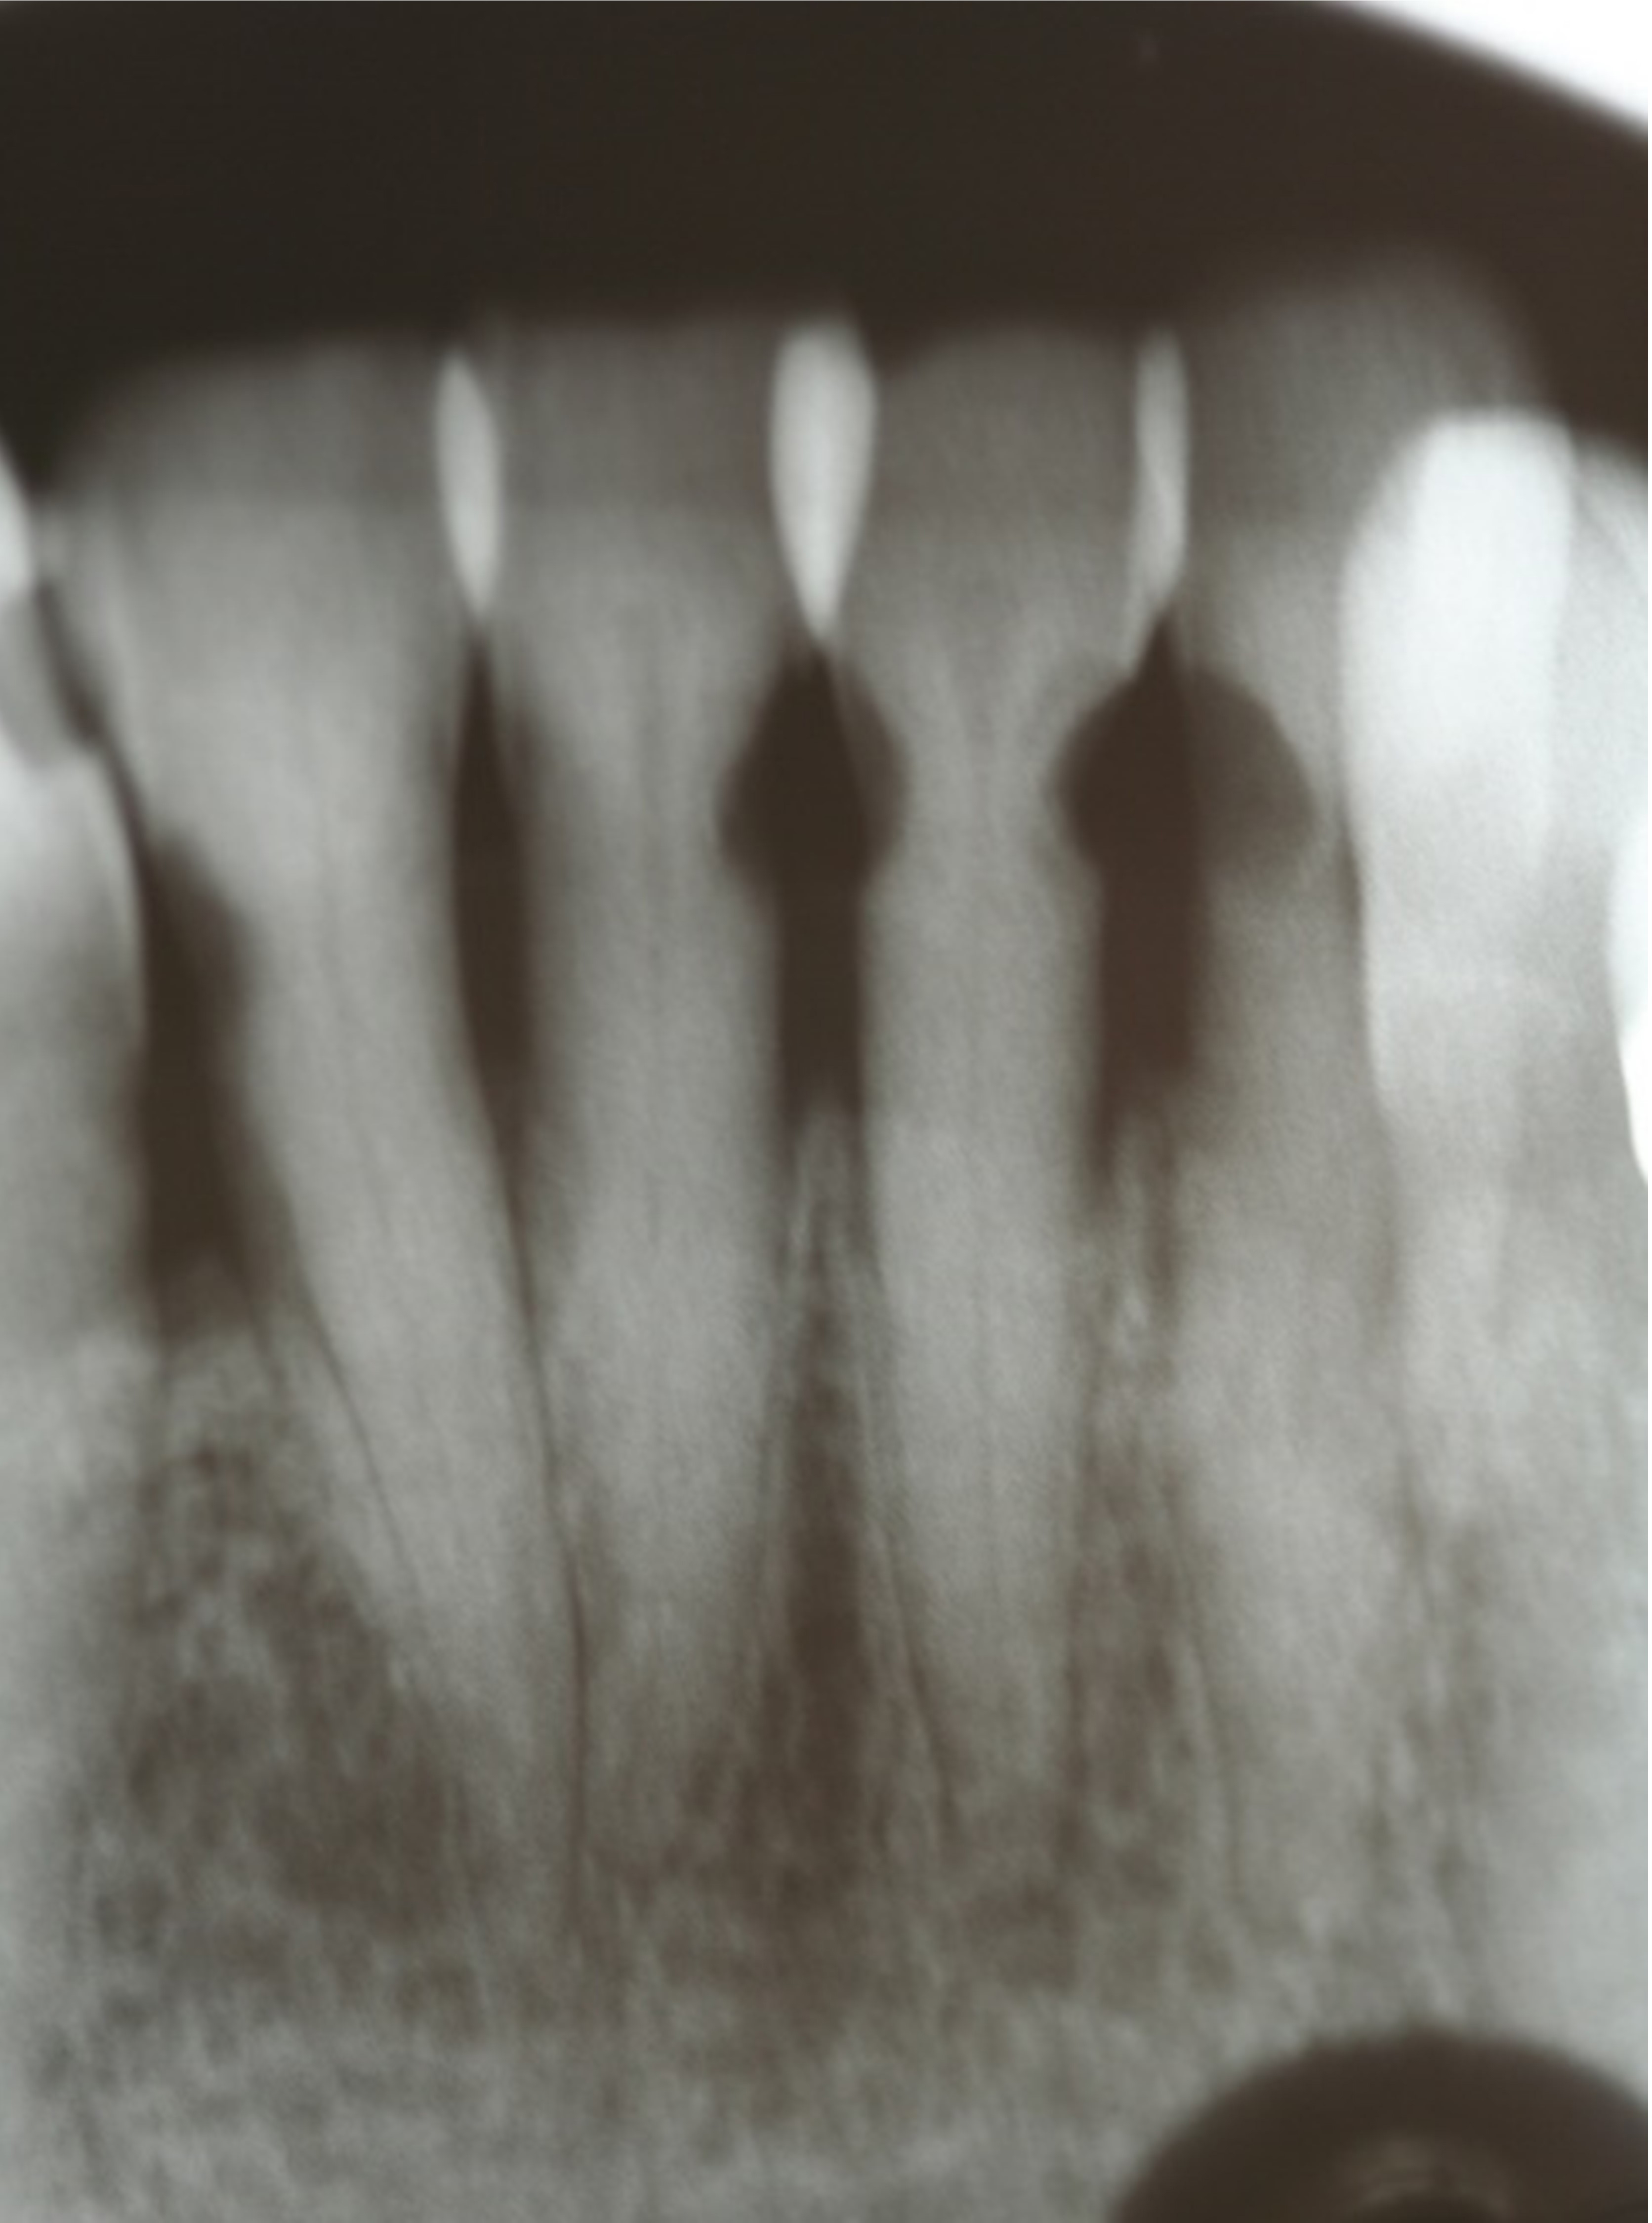

Fig 7. Use of 38% SDF to arrest root caries in permanent teeth of an elderly patient: the lower incisors were responsive to electric pulp testing with no radiographic pathology.

Figure 7